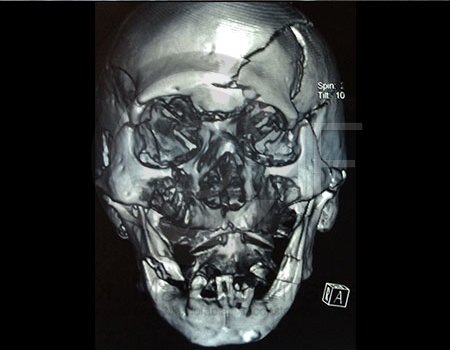

La Cirugía Oral y Maxilofacial es una de las especialidades odontológicas que brinda la posibilidad de ofrecer soluciones medicas y quirúrgicas a diferentes problemas de salud, entre los que se encuentran los defectos congénitos como el labio y paladar fisurados, las disarmonias del desarrollo facial, los traumatismos y lesiones patológicas de la región oral y maxilofacial por mencionar algunos; utilizando distintos procedimientos como la Cirugía Ortognática, la Reconstrucción mediante toma y colocación de injertos, distractores osteogénicos, regeneración tisular, implantes, etc.

CIRUGÍA ORTOGNÁTICA EN DEFORMIDADES O ASIMETRÍAS FACIALES

Es una cirugía en la que se busca mover el maxilar, mandibular y mentón o sólo una de estas estructuras para alcanzar una combinación médico-odontológica, así llegar al fin estético y funcional del aparato estomatognático y facial.

Contenido Sensible y Gráfico

Si usted no pertenece al área de la salud, las imágenes pueden ser muy explícitas.